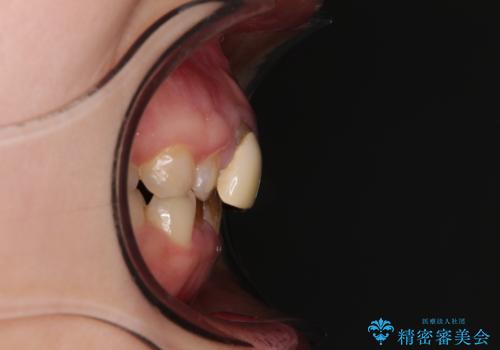

- 前歯のデコボコと、着色が著しい保険診療の前歯クラウンを気にして来院された患者様です。

左上の犬歯が埋伏しており、CT画像より萌出は困難と判断されたため、残存している歯にて歯列と咬合を整えることとしました。